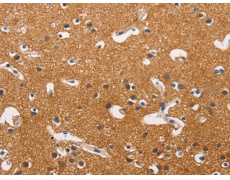

Hexokinases phosphorylate glucose to produce glucose-6-phosphate, the first step in most glucose metabolism pathways. This gene encodes a ubiquitous form of hexokinase which localizes to the outer membrane of mitochondria. Mutations in this gene have been associated with hemolytic anemia due to hexokinase deficiency. Alternative splicing of this gene results in several transcript variants which encode different isoforms, some of which are tissue-specific. |

ELISA, IHC |

IHC positive control: |

Human brain and Human thyroid cancer |

IHC Recommend dilution: |

50-200 |